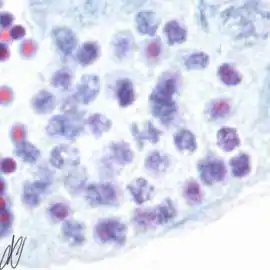

3. early spermatogonium B (eSgB) [arrows in left image]: morphologically indistinct from SgA, appears in clusters of 2-4 cells; there is moderate mitotic activity in spermatogonium B, as indicated by PCNA immunostaining [arrows in right image]; in contrast, there is only very light PCNA immunostaining in the single spermatogonium A cell [red arrows in right image]. Early SgB divide mitotically to produce:

4. late spermatogonium B: smaller than early SgB, clusters >4 cells [arrows in left image]; there is high mitotic activity, as indicated by the strong PCNA immunoreactivity [arrows in right image].

5. late spermatogonium B: clusters >4 cells [arrows]. Late SgB divides to yield smaller primary spermatocytes. Primary spermatocytes undergo meiosis, which consists of DNA duplication (yielding tetraploid cells: two copies of each chromosome, each copy consisting of two sister chromatids), genetic recombination, and two maturation divisions. The product of the first maturation division are secundary spermatocytes (diploid: one copy of each pair of chromosomes, consisting of two sister chromatids), the second maturation division yields spermatids (haploid). The first maturation division takes days, and therefore the successive stages of this division can easily be discerned:

6. spermatocyte, leptotene stage of meiotic prophase ("threadlike" appearance of chromosomes).

7. spermatocyte, leptotene stage of meiotic prophase, progressing to the zygotene stage; Note that there is staining with Putt's carbol fuchsin from this stage on, although still faint here.